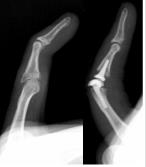

Joint Replacement

Wrist and hand joint replacement (arthroplasty) is an evolving area involving artificial implants that preserve motion when treating diseased or injured joints. Traditionally, joint fusion (arthrodesis) was the main surgical approach for most hand and wrist joint disorders. Although effective in correcting deformities and alleviating pain, joint fusion is able comes with the expense of loss of motion. With the introduction of new joint implants for the wrist and joint, corrective surgery with the preservation of motion of the joint has become possible, ultimately improving the patient’s quality of life.

Replacement of a post traumatic arthritic proximal interphalangeal joint